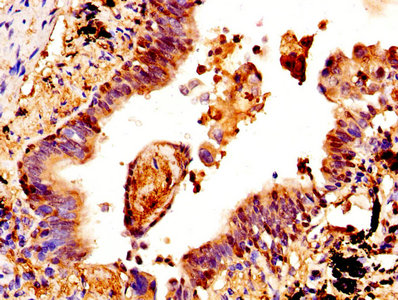

IHC image of CSB-PA006099DA01HU diluted at 1:400 and staining in paraffin-embedded human lung cancer performed on a Leica BondTM system. After dewaxing and hydration, antigen retrieval was mediated by high pressure in a citrate buffer (pH 6.0). Section was blocked with 10% normal goat serum 30min at RT. Then primary antibody (1% BSA) was incubated at 4°C overnight. The primary is detected by a biotinylated secondary antibody and visualized using an HRP conjugated SP system.